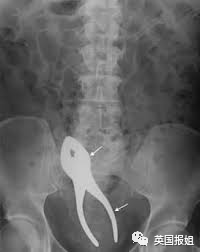

比如一把家门钥匙:

比如一个钳子:

比如手机:新闻报道称这名佐治亚州的忙碌男子,在把手机塞进身体后,仍不断接到电话,导致取出工作一度陷入僵局。

比如人人都知道放进去就取不出来的灯泡:

比如风评被害的巴斯光年: